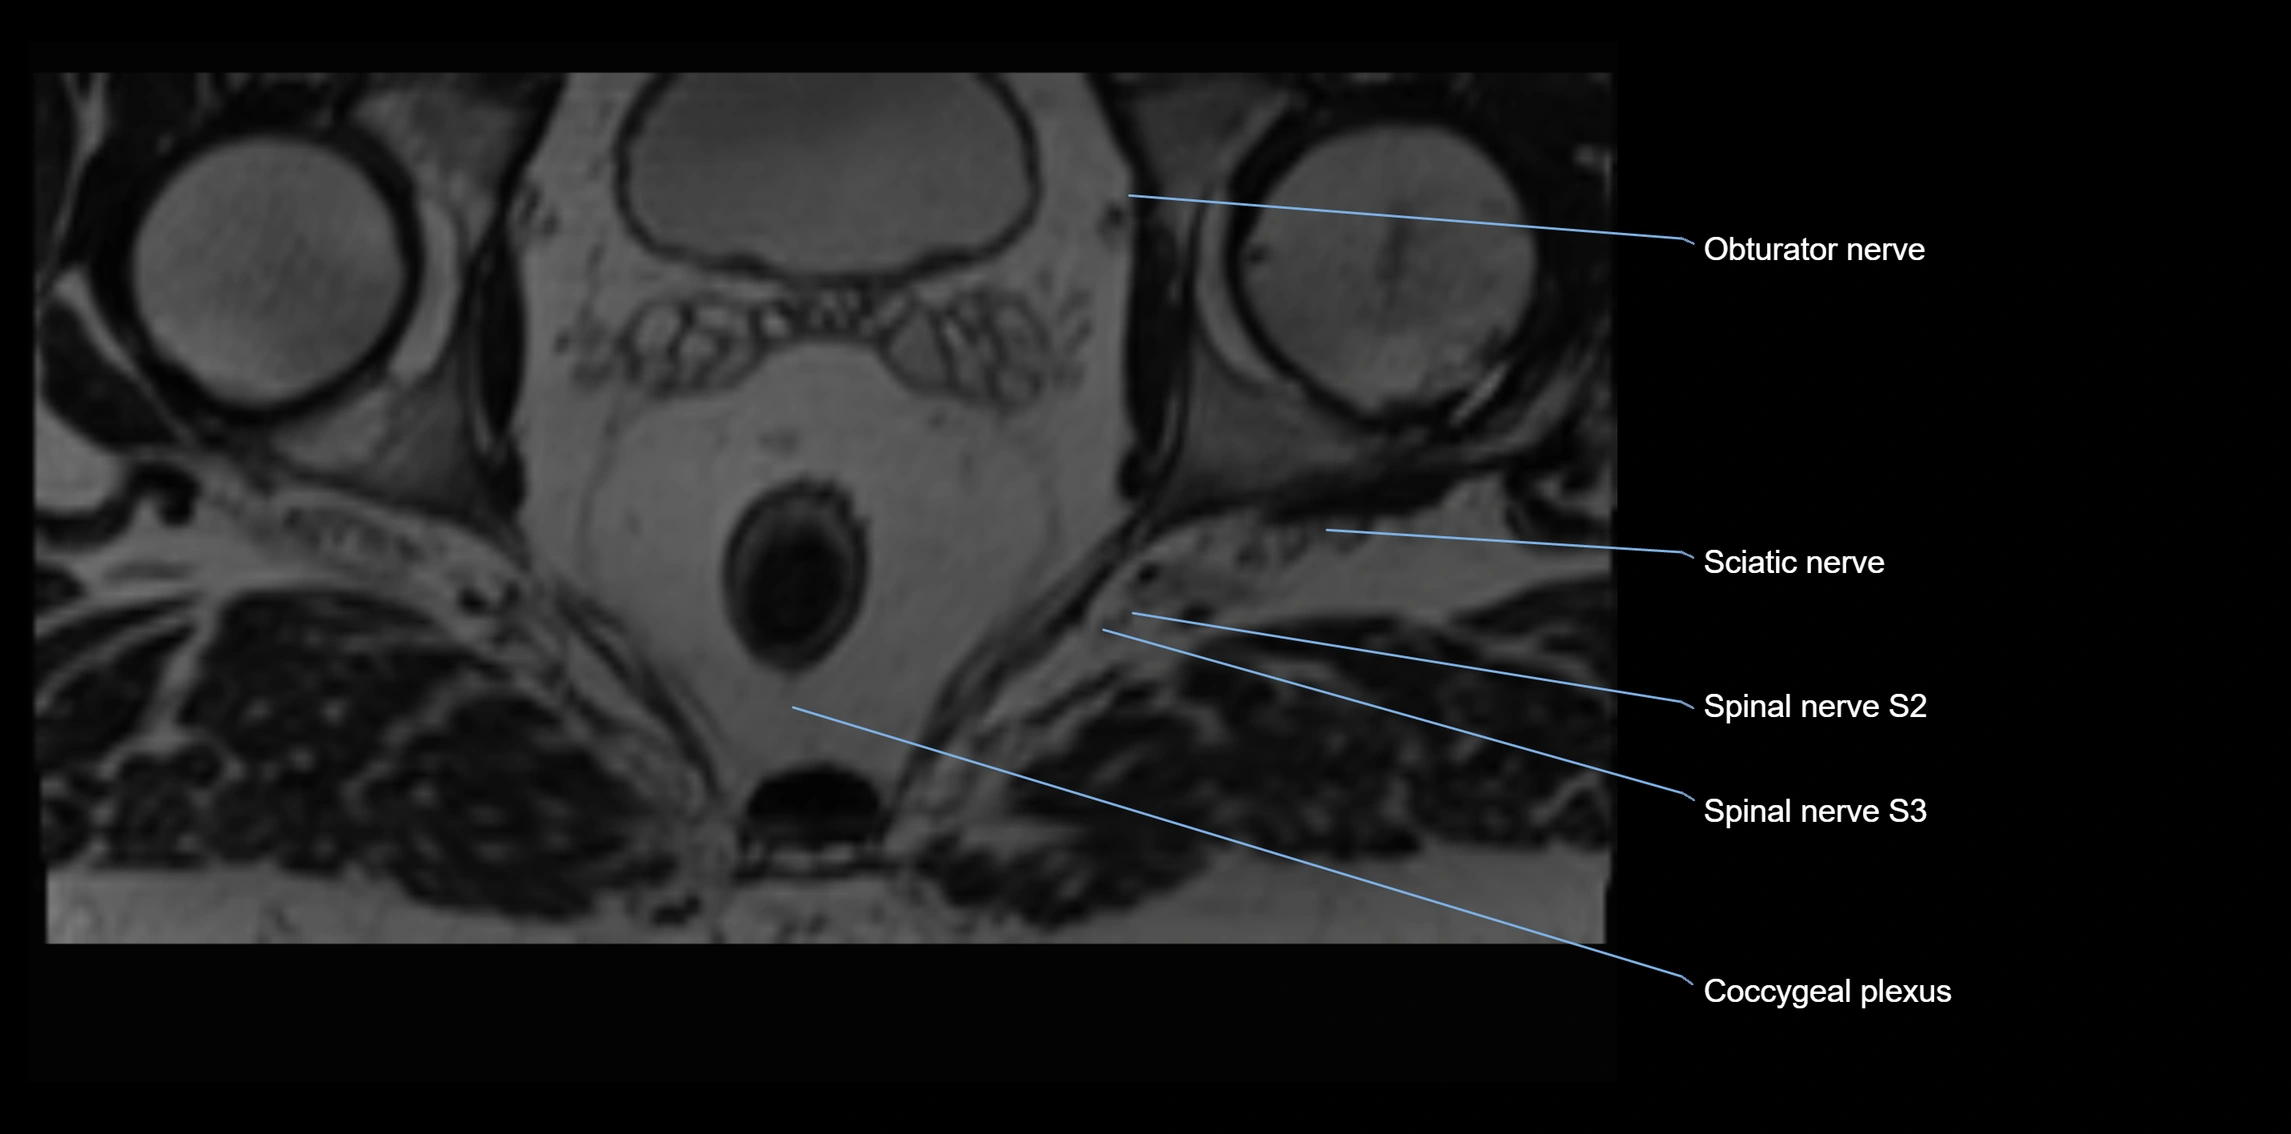

MRI Appearance

T1-weighted images:

• Nerve appears as a very thin low-to-intermediate signal intensity structure

• Surrounded by bright fat, aiding visualization

T2-weighted images:

• Nerve shows intermediate to mildly hyperintense signal compared to muscle

• Pathological involvement appears brighter

STIR (Short Tau Inversion Recovery):

• Normal nerve appears dark

• Inflamed or entrapped nerve appears bright hyperintense

T1 Fat-Sat Post-Contrast:

• Normal nerve enhances minimally

• Pathologic nerve (neuritis, entrapment, tumor infiltration) shows focal or diffuse enhancement

3D T2 SPACE / CISS:

• Nerve appears intermediate to mildly hyperintense compared to muscle

• Surrounded by bright fat or CSF, improving visualization

• Best sequence for mapping small pelvic nerves such as the anococcygeal